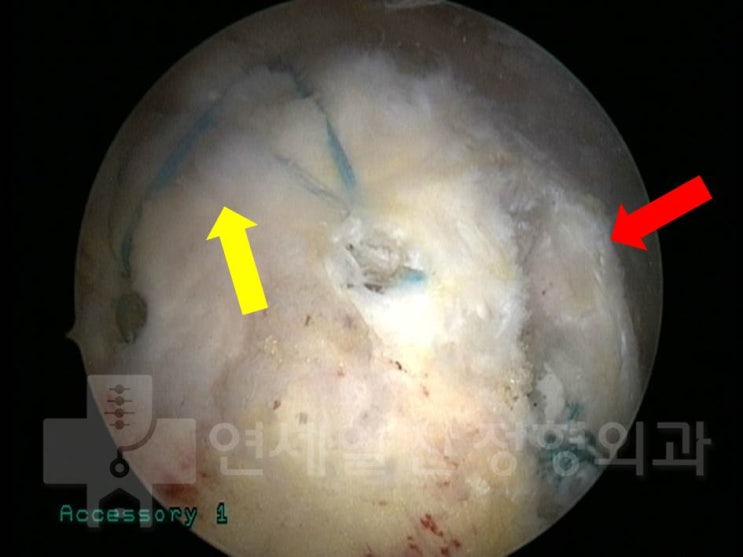

거대한 석회성 건염에서 관절경을 통한 석회 제거술 및 극상근 봉합술(side to side)

43에 여자 환자로 우측 어깨의 극심한 통증을 주소로 내원하였다. 환자는 내원 일주일 전부터 극심한 통증...

석회성 건염에서 관절경하 석회 제거술의 결과

61세 여자 환자로 좌측 어깨의 극심한 통증을 주소로 내원하였다. 환자는 타병원에서 석회성 건염을 진단 ...